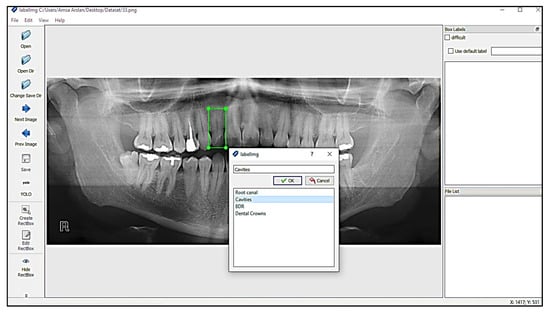

4.3. Image Annotation

One of the significant concepts in deep learning is image annotation, by which we labelled specific parts of images for training the model. The YOLOv3 model, which accepts annotation files in “txt” format, was used. The image and the annotation file must be saved in the same archive. Each row in the annotation file represents a single bounding box in the image and includes the information listed below.

“<Object-class-id> <center-x> <center-y> <width> <height>”

These parameters are explained as follows:

• Objects-Class-Id: an int-type value that shows a class. The range of object-class-id is 0 to the number of classes−1. We have a total of 4 classes, so the range of object-class-id is 0 to 3.

• Center-x & Center-y: the center-x and center-y are the “center coordinates” of the bounding box.

• Width and Height: these are the dimensions of the bounding box.4.4 LabelImg.

LabelImg is a free open-source tool for graphically labelling images. It is written in Python and has a QT-based graphical user interface. It is a quick and simple method for labelling a few hundred images for object detection. Labeling process with LabelImg is shown in Figure 4.

Annotations were stored in the PASCAL VOC format as XML files which ImageNet uses [30]. It also supports the YOLO and Create ML formats. The annotation file for YOLO in .txt format is shown in the Figure 5: